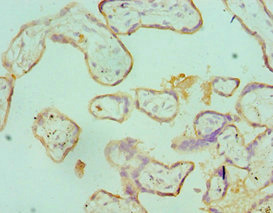

Immunohistochemistry of paraffin-embedded human placenta tissue using CSB-PA020888ESR2HU at dilution of 1:100